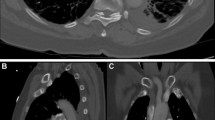

We found that the diameter of the main pulmonary artery and the presence of intraventricular septal bowing were associated with short-term clinical deterioration after PE (Table 3, Figs. 1 and 2). These are fast and simple measurements of cardiac and vascular dimensions available from any CTPA and our results are generally consistent with other studies [7, 9, 19, 21,22,23,24,25]. However, other studies evaluating CTPA measures of RV function have used different follow-up periods or strategies of measurement. For example, Moroni et al. followed patients for 3 months [22], and Apfaltrer et al. [9] measured RV and LV diameters at their broadest and not at the level of the leaflets or at least at the same level in the respective ventricles. Our follow-up period reflects short-term clinical deterioration that (A) is more likely to be directly related to the PE than longer term outcomes and (B) occurs during a typical hospitalization for PE and during a time period where acute intervention (e.g., thrombolysis) might be considered.

Representative images of pulmonary embolism with and without main PA dilatation. a CTPA from a patient, that despite PE has a normal, narrow main PA of 22.3 mm. b How PE has caused dilatation of the main PA to 30.2 mm. PA, pulmonary artery; CTPA, computed tomography pulmonary angiography; PE, pulmonary embolism; Ao, aorta

Signs of RV dysfunction on CT. Panels a and b stem from the same two patients as in Fig. 1. a A normal interventricular septum bowing towards the RV. b An enlarged RV with high intraventricular pressure causing the leftward shift and bowing of the septum. This may compromise LV preload, LV function, and the systemic circulation, too. See text for further details. CT, computed tomography; RV, right ventricle; LV, left ventricle

Acute PE causes mechanical obstruction and release of pulmonary vasoconstrictors [3]. The combination of obstruction and vasoconstriction increases pulmonary vascular resistance and causes blood to pool in the (normally compliant) pulmonary arteries, thereby causing PA distension (Fig. 1). However, the main pulmonary artery loses compliance the more it is stretched and does have a limit of distensibility. The value of 29.0 mm has been established as the maximal normal value of main PA diameter and suggested as cutoff to detect pulmonary hypertension (PH) [26, 27]. In our study, the median PA diameter in patients with adverse outcomes was 29.9 mm with a broad IQ range. This may limit its clinical utility. Furthermore, one might expect the progress of PA dilatation to be different between acute PE and slowly progressing PH. Therefore, while we do see a statistically significant association between PA diameter and short-term clinical deterioration, the limited total distensibility of the main PA in acute PE may mean that the OR (1.08, per 1 mm increase) we found is of limited clinical relevance. Other studies also find the PA diameter only to be a weak predictor [7, 8, 22, 25, 28, 29].

We also found that bowing of the interventricular septum was associated with a more than twofold risk of clinical deterioration, with a p value bordering statistical significance (p = 0.055). Septal bowing is a sign of high RV intraventricular pressure with a decreasing trans-septal pressure gradient. Leftward shift of the septum and RV output failure limits LV filling and compromises LV output and, accordingly, cardiac output and mean blood pressure. Decreased coronary perfusion pressure worsens RV oxygen supply, causing RV ischemia and will further worsen RV function [2] (see Fig. 2b). Abnormal septal positioning has been shown to be a negative predictor in both CT and echocardiography [8, 13] but not consistently [24, 25]. This discordance may be explained by a relatively poor interobserver agreement in the detection of septal bowing [30], which corresponds to the low kappa value in the present study. The limited reliability in the interpretation of septal bowing may need to be acknowledged in clinical practice. On the contrary, as septal movements vary through the cardiac cycle [31], non-gated CT may produce false-negative measurements yielding an even higher OR. Collectively, despite the kappa value and due to the high OR, we believe that finding of septal bowing on CTPA is the most clinically relevant finding of the present study, and emergency physicians and radiologists may find this observation useful.